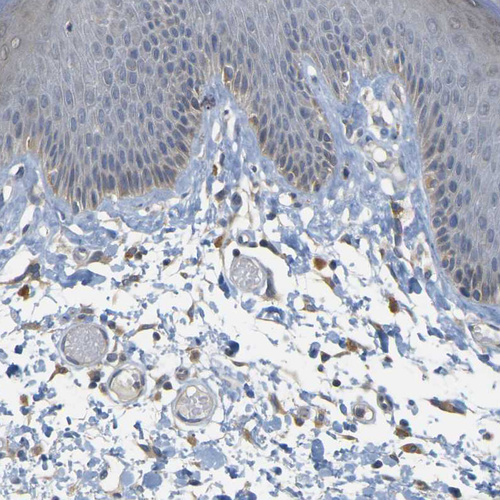

Immunohistochemistry analysis in human cerebral cortex and skin tissues using HPA014266 antibody. Corresponding GDAP1 RNA-seq data are presented for the same tissues.